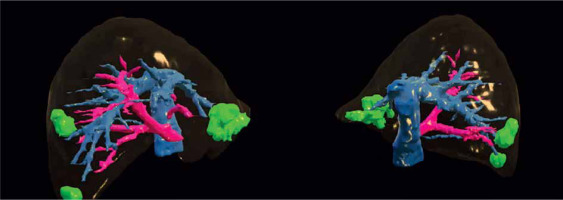

Preoperative imaging is necessary in LLS both for oncological staging and planning the operation with its potentially expected difficulties. The main imaging devices used before LLS are computed tomography (CT) and magnetic resonance imaging (MRI) [5], with CT being more effective in evaluating tumors in relation to large vessels and MRI being more accurate in assessing tumors’ character and evaluating bile ducts [6]. PET-CT imaging is used only in selected cases [7]. 3D printings of liver models are not widely used because of their high cost, but they may impact surgeons’ intraoperative decisions [8]. Moreover, 3D preoperative liver reconstructions, available preoperatively as well as intraoperatively, may be helpful in selected cases (Photo 1) [9]. 3D reconstructions may be helpful in carefully planning difficult liver surgeries including tumor size, location and its relation to large liver vessels [10]. Nevertheless, more prospective studies are needed to possibly introduce this novel technique to everyday practice.